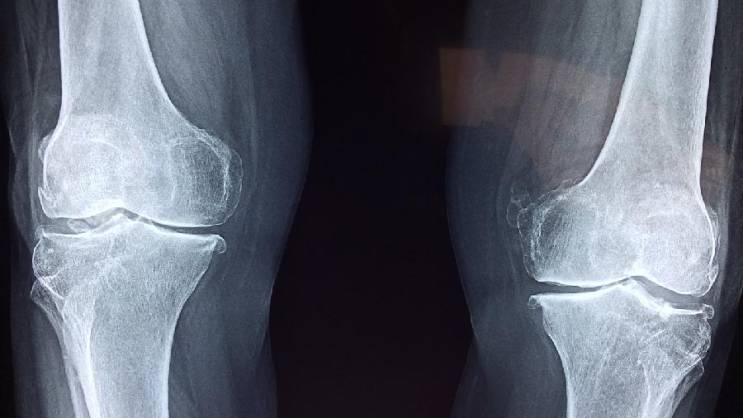

Foto: Ilustracija, Pixabay

Kosti često oslabe i postanu lomljive bez ikakvih simptoma, a toga postajemo svesni tek kada dođe do preloma.

„Pošto je slabljenje kostiju često neotkriveno, prvi način na koji ljudi mogu da saznaju koliko su im kosti zdrave je skeniranje gustine kostiju, ili DEKSA skeniranje, koje se preporučuje za svaku ženu stariju od 65 godina, mlađe žene u riziku od razvoja osteoporoze i muškarce starije od 70 godina“, rekao je za „The Parade“ dr Heter L. Hoflih.

Endokrinolog Sara Fišman potvrđuje da je ovo važan test.

„Nažalost, osteoporoza i osteopenija su često tiha stanja. Većina ljudi ne oseća ništa u svojim kostima dok ne dođe do preloma“, upozorila je ona.

Međutim, prema riječima dr Fišman, postoji rani znak da kosti slabe, a to je skupljanje.

„Dok neki ljudi vjeruju da je smanjenje obima zgloba znak slabljenja kostiju, to je zapravo manje tačan znak od gubitka visine“, primetila je ona.